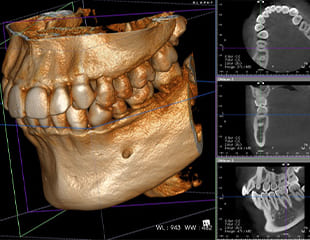

治療に必要な三種の神器

マイクロスコープ・CT・CAD-CAMシステム

歯科用CT検査システム

コージ・ヤマモト歯科医院では、歯科用CT検査機器を取り入れております。